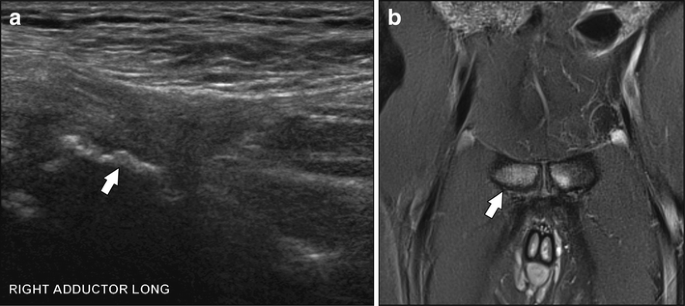

• Imaging of Athletic Pubalgia (with Turf Toe) CANCELLED

• Imaging of Athletic Pubalgia